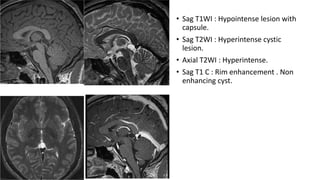

• Sag T1WI : Hypointense lesion with

capsule.

• Sag T2WI : Hyperintense cystic

lesion.

• Axial T2WI : Hyperintense.

• Sag T1 C : Rim enhancement . Non

enhancing cyst.